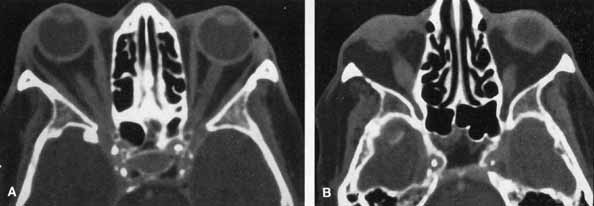

these patients 81 ORBIT. HZO orbital myositis resulting proptosis and extraocular muscle palsies

has been described.82 HZO can produce ptosis from a secondary Horner's syndrome. Kattah

and Kennerdell83 reported on two patients with orbital apex syndrome (optic neuropathy

with complete ophthalmoplegia and anesthesia), associated with

meningoencephalitis. A patient with HZO with proptosis, optic neuropathy, and

restriction of abduction and up-gaze showed marked enlargement

of the inferior and medial rectus muscles on computed tomography (CT) scanning, which resolved with systemic corticosteroid

therapy (Fig. 19A and 19B).84 Orbital myositis is a cause of HZO-associated ophthalmoplegia, an

entity most often attributed to primary or secondary cranial nerve

VZV involvement.  Fig. 19 Orbital myositis in herpes zoster ophthalmicus (HZO). Axial contrasted

orbital computed tomographic scan, demonstrating enlargement

of right medial rectus (A) and right inferior rectus (B) muscles. Fig. 19 Orbital myositis in herpes zoster ophthalmicus (HZO). Axial contrasted

orbital computed tomographic scan, demonstrating enlargement

of right medial rectus (A) and right inferior rectus (B) muscles.

|